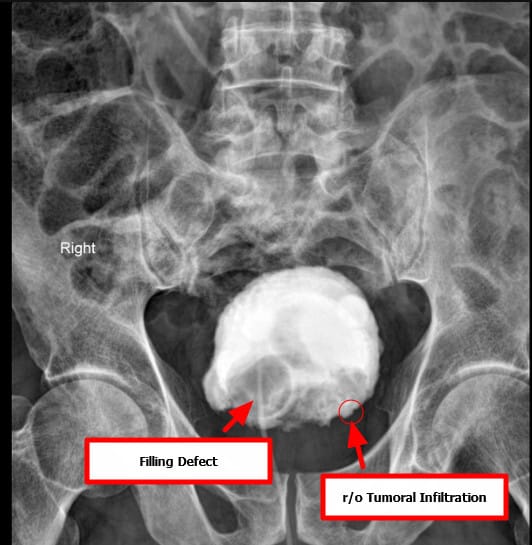

방광암을 초기에 평가할 때 가장 흔히 시행

요로조영술 (Intravenous Urography, IVU)

조영제를 통해 요로계 구조를 간접적으로 시각화

[진단]

– 소변검사: 혈뇨 확인.

– 소변세포검사: 암세포 확인 가능.

– 방광경검사(Cystoscopy): 진단의 gold standard, 직접 종양 확인 및 조직생검 가능.

– 영상검사(CT urography, MRI): 종양의 범위 및 전이 평가.

– 병리검사: 요로상피암(urothelial carcinoma), 편평상피암, 선암 등 조직학적 아형 구분.